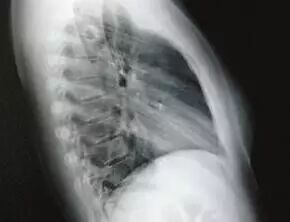

虽然经过对症药物治疗,萧萧体内的寄生虫已经被杀灭,但医生表示,肺吸虫已经对萧萧的身体造成了永久性的伤害。“通过CT检查,在萧萧的肺部可见到明显的空洞,这正是肺吸虫游走肺内留下的痕迹。”

肺部空洞 资料图片